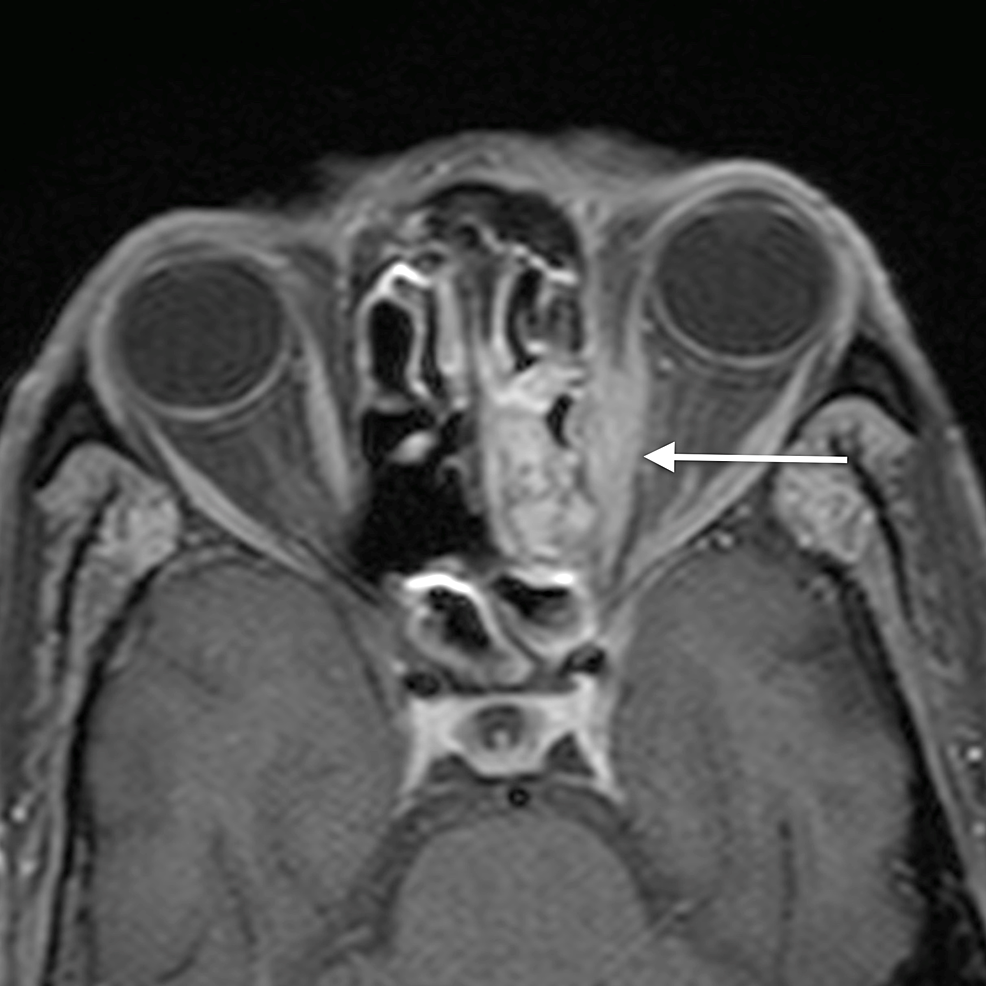

The main complications of orbital cellulitis (Figures 2-4) encountered in our study were:

1. An orbital abscess (Figures 5-6);

2. Preseptal cellulitis and abscess (Figures 7-8);

3. Periorbital cellulitis (Figures 9-10);

4. Dacryoadenitis (Figures 11-12);

5. Optic neuritis/perineuritis (Figure 13);

6. Cavernous sinus thrombophlebitis and thrombosis (Figure 14).

The most common complication of orbital cellulitis was orbital/periorbital abscess formation (eight cases, 53.3%), followed by optic neuritis (four cases, 26.67%), intracranial involvement (four cases, 26.67%), dacryoadenitis (three cases, 20%) and cavernous sinus thrombophlebitis (three cases, 20%).